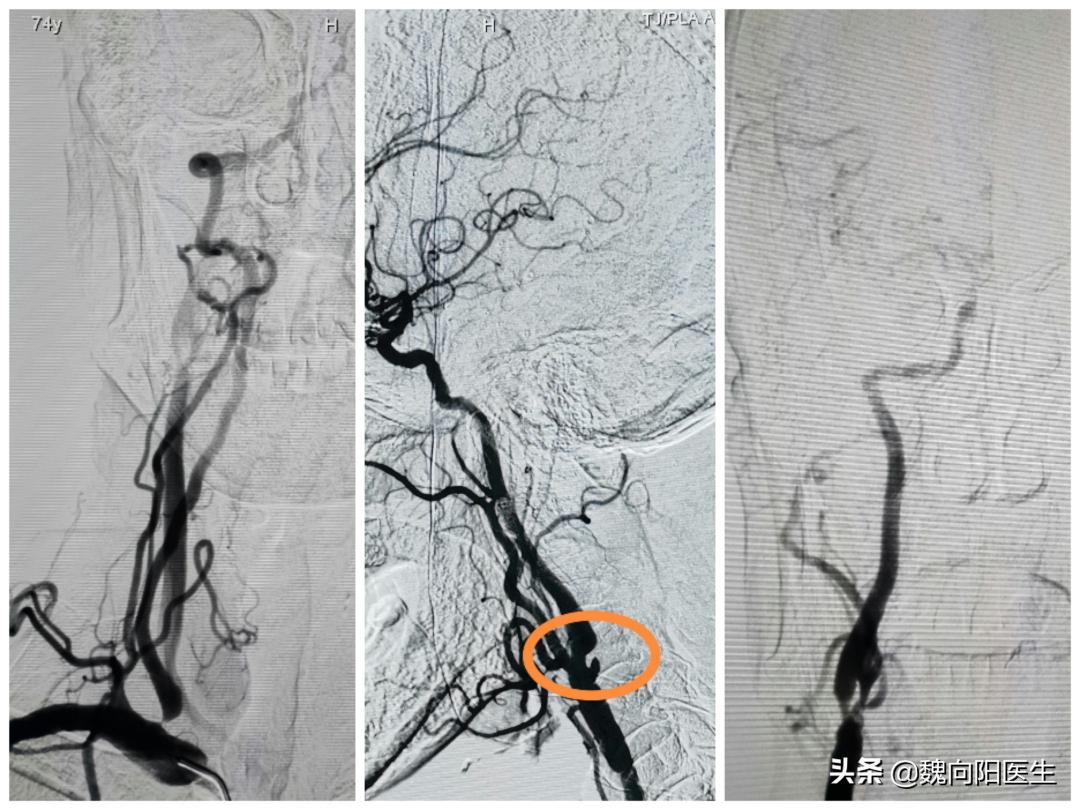

在老伴的陪同下来到医院就诊,在做完头颈CTA后发现通往大脑的四根血管堵了一根,另外三根都存在明显的狭窄,老张多次的晕厥都是由于短暂性脑缺血导致的。如果脑缺血的时间超过5-10分钟,患者大脑可能会导致不可逆性的坏死,很容易遗留后遗症,甚至危及生命。

在给患者安排住院之后,完善了相关的检查及化验,考虑患者双侧颈动脉及右侧椎动脉均为重度狭窄(狭窄>75%),因此建议行血管支架治疗,但是考虑患者心率较慢,平常在60次/分钟,在进行颈动脉支架时,很容易导致心率减慢、血压降低,甚至严重到心率骤停。

提前联系了心脏科,在术前提前植入临时心脏起搏器,并术中备好升压药物,以防手术中出现心率减慢和血压降低后,对患者造成不可预估的伤害。果不其然在球囊扩张颈动脉窦时,患者的血压及心率明显下降,幸好提前植入的心脏起搏器自作用了,在预设的心率位置时帮助心脏跳动。

多次反复的晕厥,考虑到存在短暂性脑缺血发作,该患者主要是由于颈动脉及椎动脉狭窄导致。一般针对这样的患者建议分次支架植入术,以减少手术中的风险。但是该患者由于费用有限,且不想第二次接受手术,因此考虑给予一次手术解决三根问题。这样不但省钱,还可以使患者少受罪。

最主要的风险就是颈动脉窦反射,在颈动脉支架植入过程中,由于刺激颈动脉窦,会导致反射性心率减慢和血压下降,严重时会导致心脏骤停。